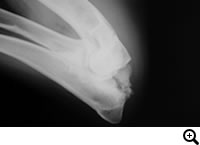

手根関節脱臼 / 亜脱臼 / 不安定症 / 過伸展

症状:前足がオットセイのような形になる、手首が床に着く、前足の跛行、手首の関節の腫れや痛み

手根関節脱臼 / 亜脱臼 / 不安定症 / 過伸展とは

落下やジャンプに伴って起こる靭帯損傷や、免疫介在性関節炎、糖尿病、クッシングなど内科疾患に関連して起こる靭帯変性により生じる手根関節の不安定性

診断

レントゲン検査など

治療

外科適応の場合は全関節固定術、部分関節固定術、スーチャーアンカー法などをおこない、手根関節を固定します